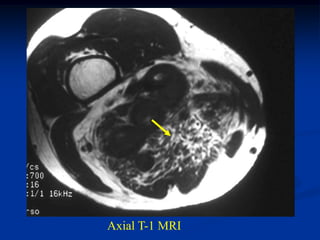

Case #1188

72 year female with

intramuscular lipoma

mid arm

Axial T-1 MRI

Case #1188 72 yearfemale with intramuscular lipoma mid arm